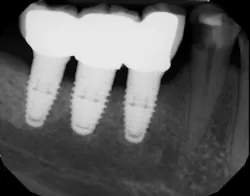

Because ICL between an implant restoration and an adjacent tooth has been highly correlated with the development of caries, a significant health concern arises in individuals with high caries rates who are receiving dental implants (figure 1). Clinicians and allied personnel should be familiar with the factors that contribute to implant-induced decay and are more likely to predispose patients to open contacts. Otherwise, vulnerable patients could be missing out on valuable screening and preventive measures.

Figure 1: Interproximal contact loss between an implant restoration and an adjacent tooth.